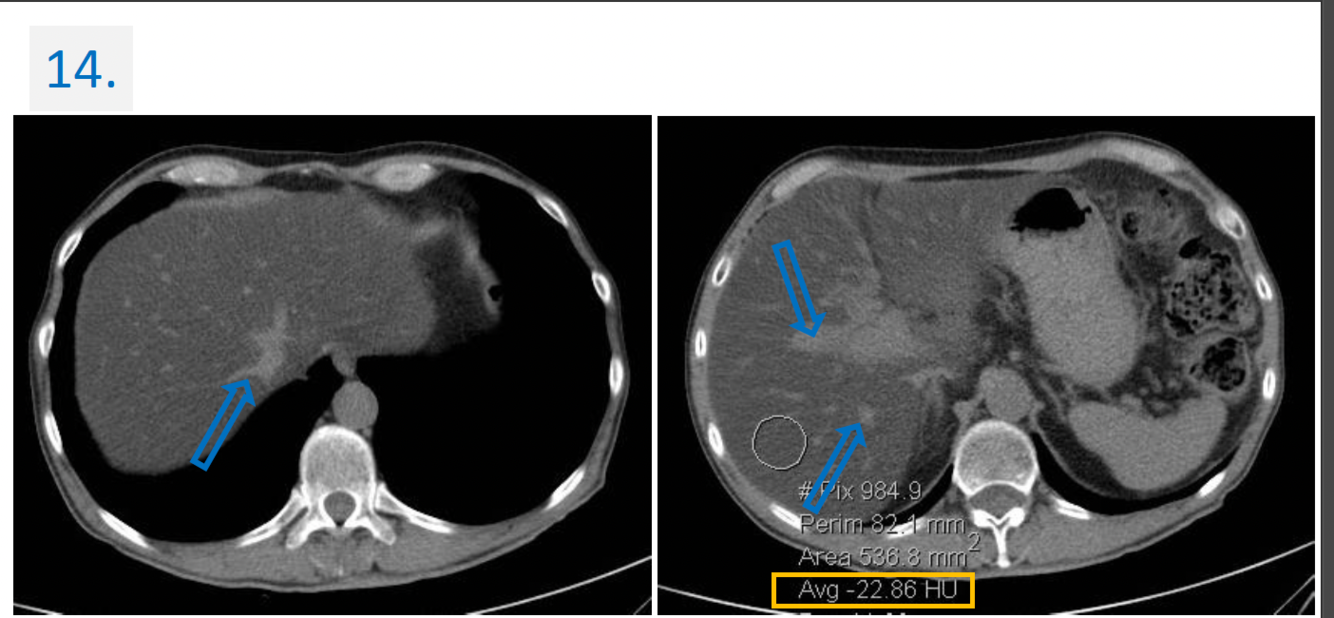

14

14.

Modality:

Noncontrast CT

Region:

Upper abdomen, axial views

Radiologic sign:

-Diffusely & homogenously decreased density (cca. -20 HU) of the liver

(normal density is cca. 50-60 HU).

-The vessels (blue arrows) → denser -relative to the liver parenchyma-

Diagnosis:

Steatosis Hepatis (Fatty liver)